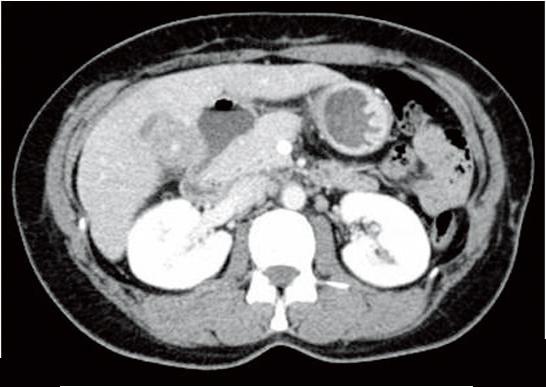

あとは、CTで肝臓には何もなくて胆嚢がよくわからない(?)、ERCPで胆管・膵管とも拡張なく綺麗に描出されている(一方で胆嚢は描出されてない)、、といったあたりが読めれば、b 胆嚢癌とわかる。